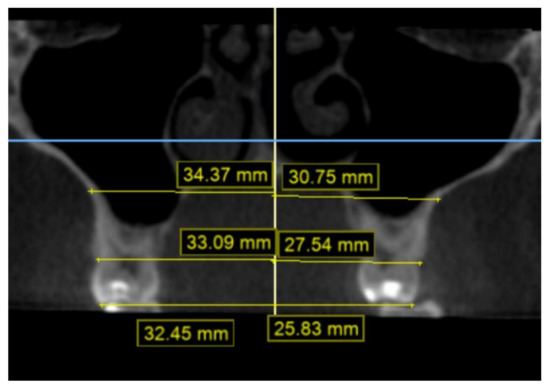

2.2. Methodology of Measurements